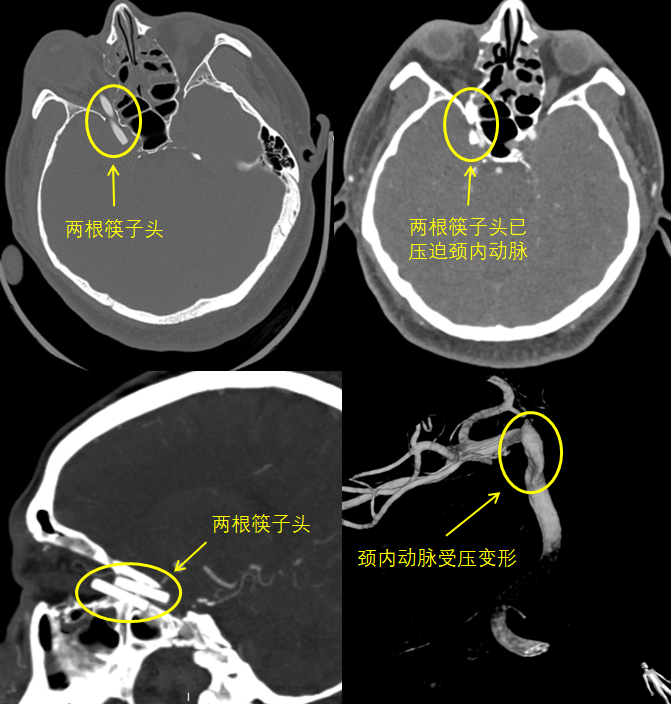

头颅CT显示:筷子头大部分位于眼眶内,但其最深处已穿过眶上裂,进入颅内,压迫颈内动脉。

闫伟解释说,眶上裂是很多控制眼球的神经与大脑相连接的孔道,筷子穿过这个孔道极大可能会损伤这些神经。而颈内动脉是颅内最大的动脉,一旦破裂出血,会造成致命的严重后果。

患者病情非常危急,一方面大动脉受压,随时可能大出血危及生命,而动脉受压如果出现脑血流不通畅也可能造成大范围的脑梗塞;另一方面,筷子留置在眼眶内,时间久了会出现感染,细菌可能进入颅内造成严重后果。

患者的病情复杂,当务之急是把筷子头取出。但是,取筷子的最大风险在于颈内动脉大出血,一旦出血需当即处理,否则数分钟内即会有生命危险;此外,如何在肿胀的眼眶内准确找到筷子,也很有难度。